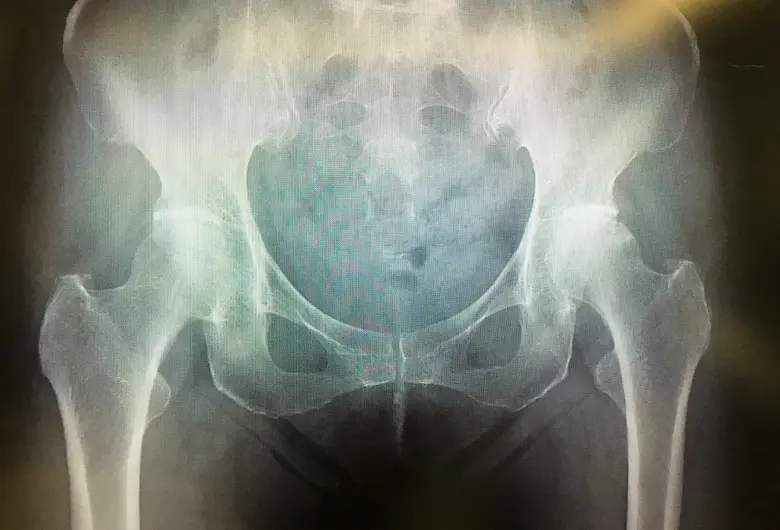

手術前

手術後